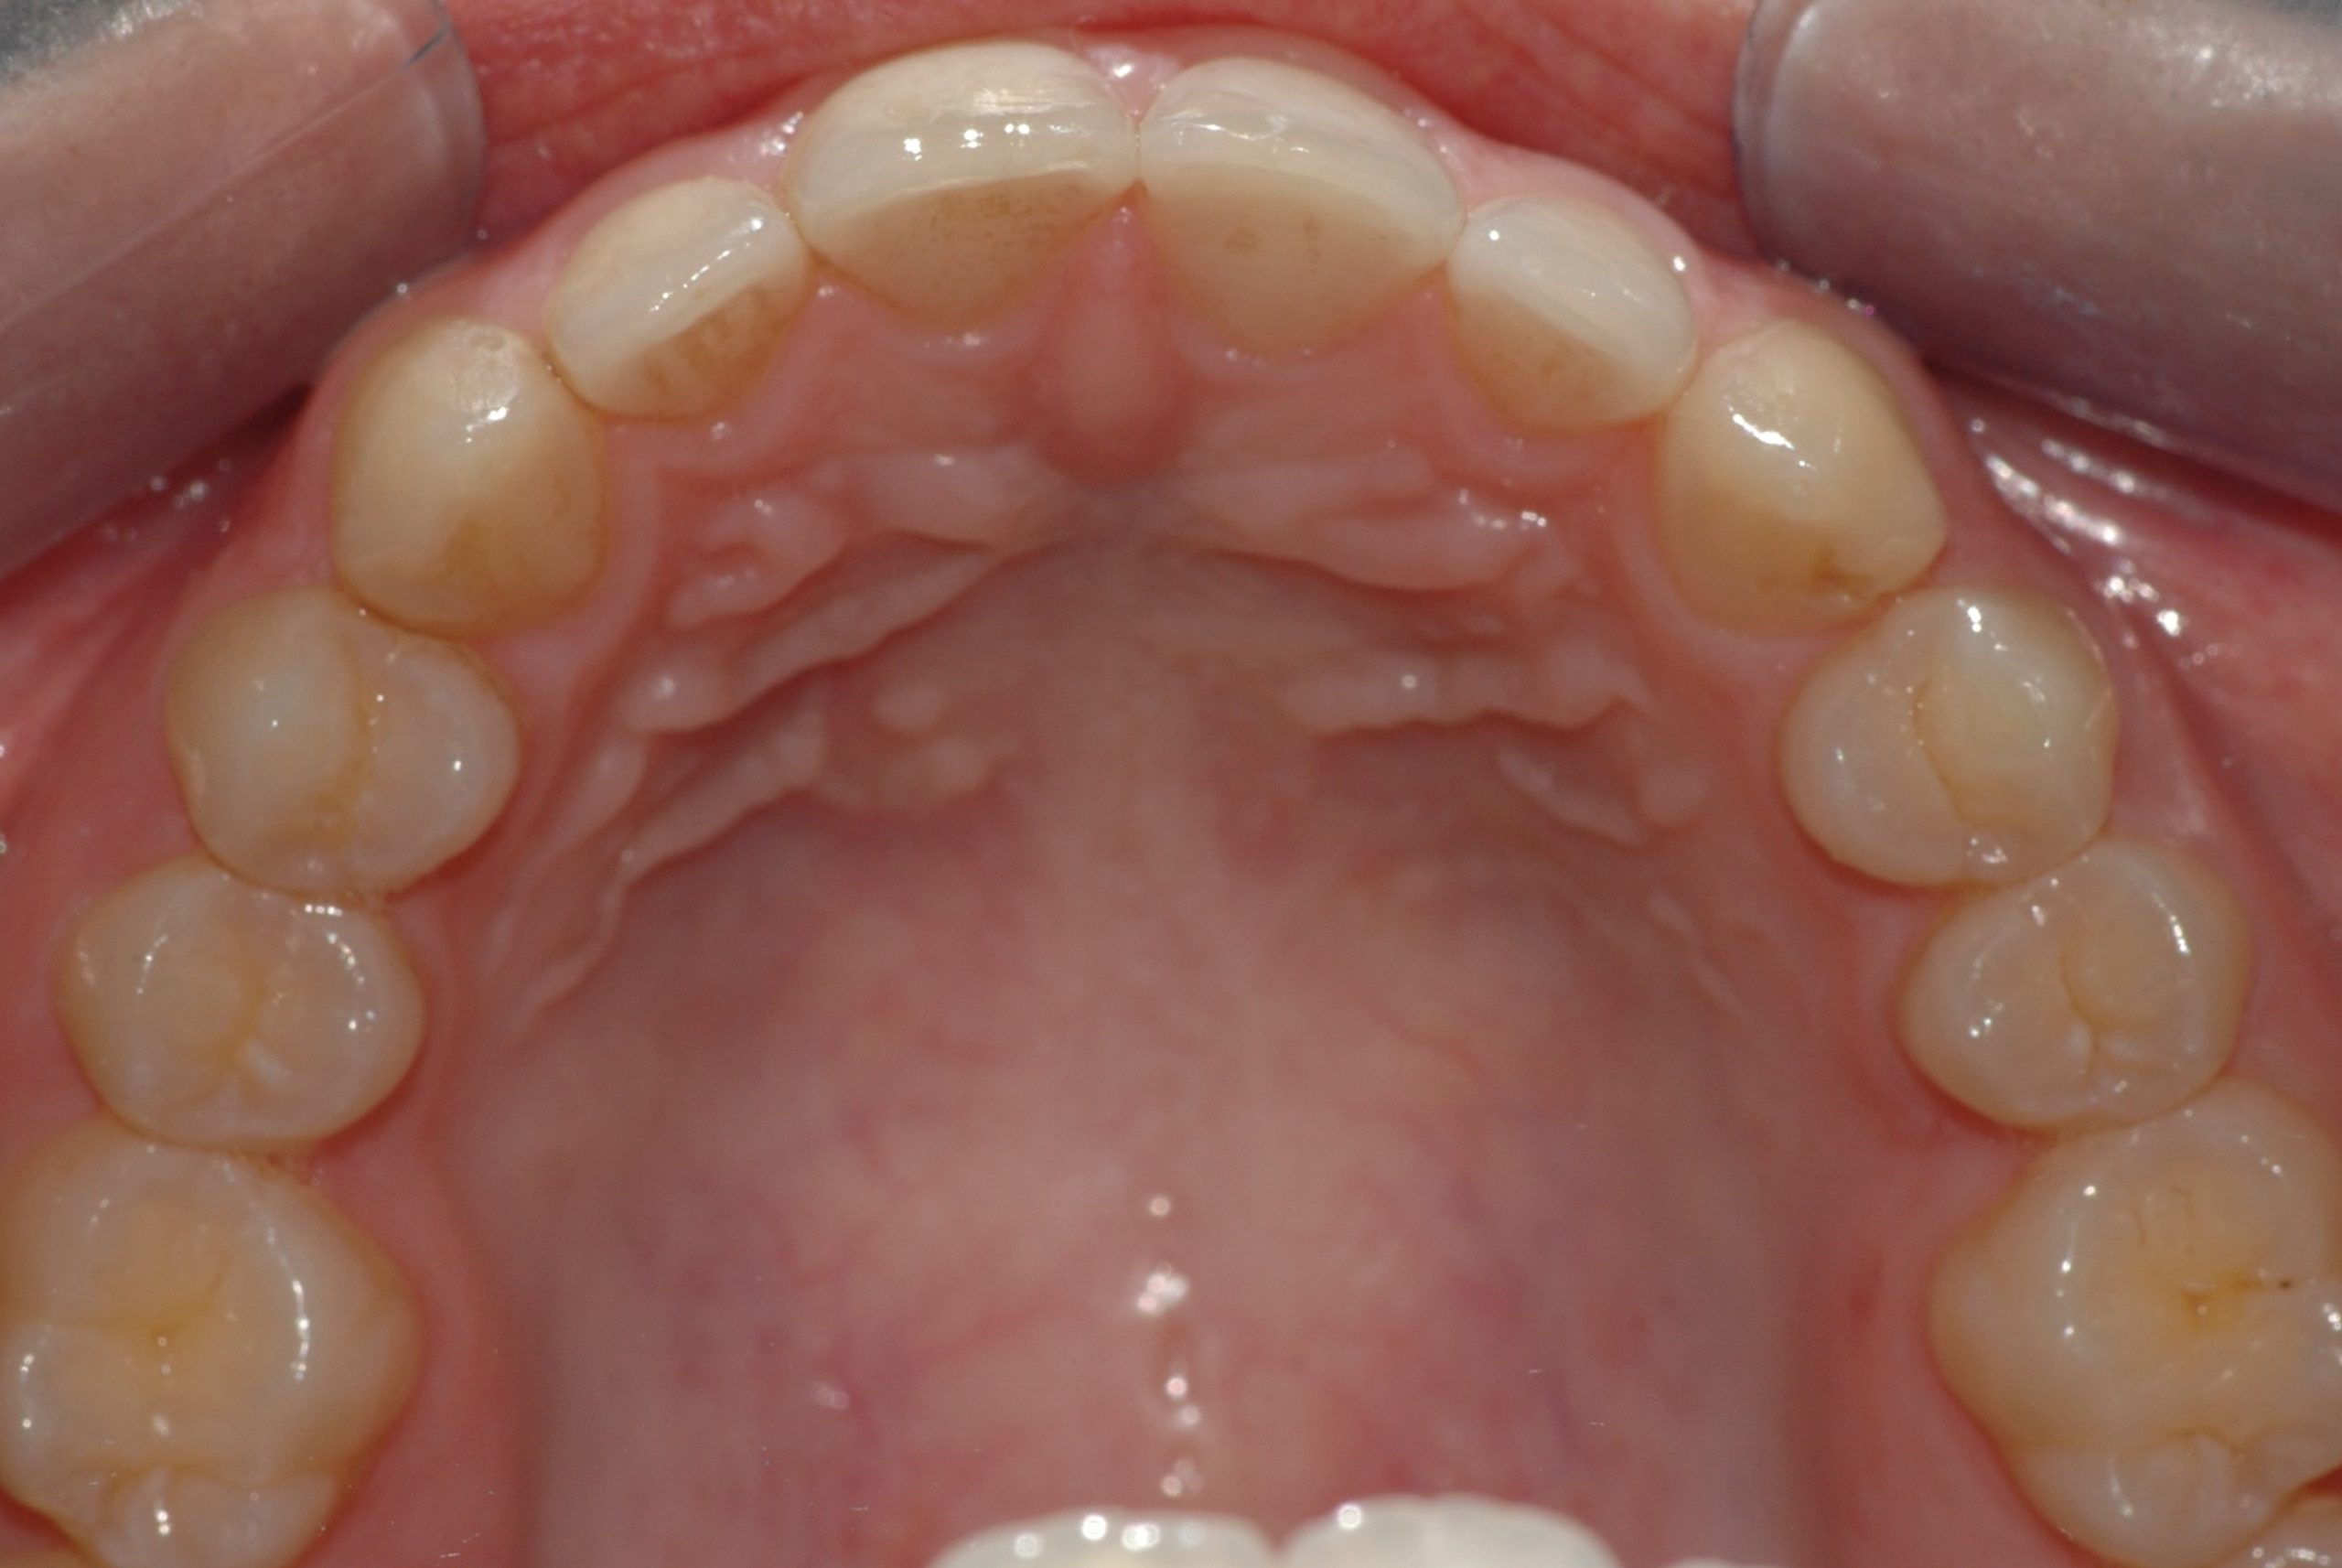

Caso clinico

La paziente si presenta con la richiesta di chiudere il diastema presente tra gli incisivi superiori, sia per motivi estetici, sia a causa di una forte infiammazione gengivale provocata dall’intasamento alimentare (food impaction) nello spazio aperto. In 6 mesi di tempo, il trattamento tramite allineatori, ha chiuso lo spazio e risolto il problema a livello gengivale.